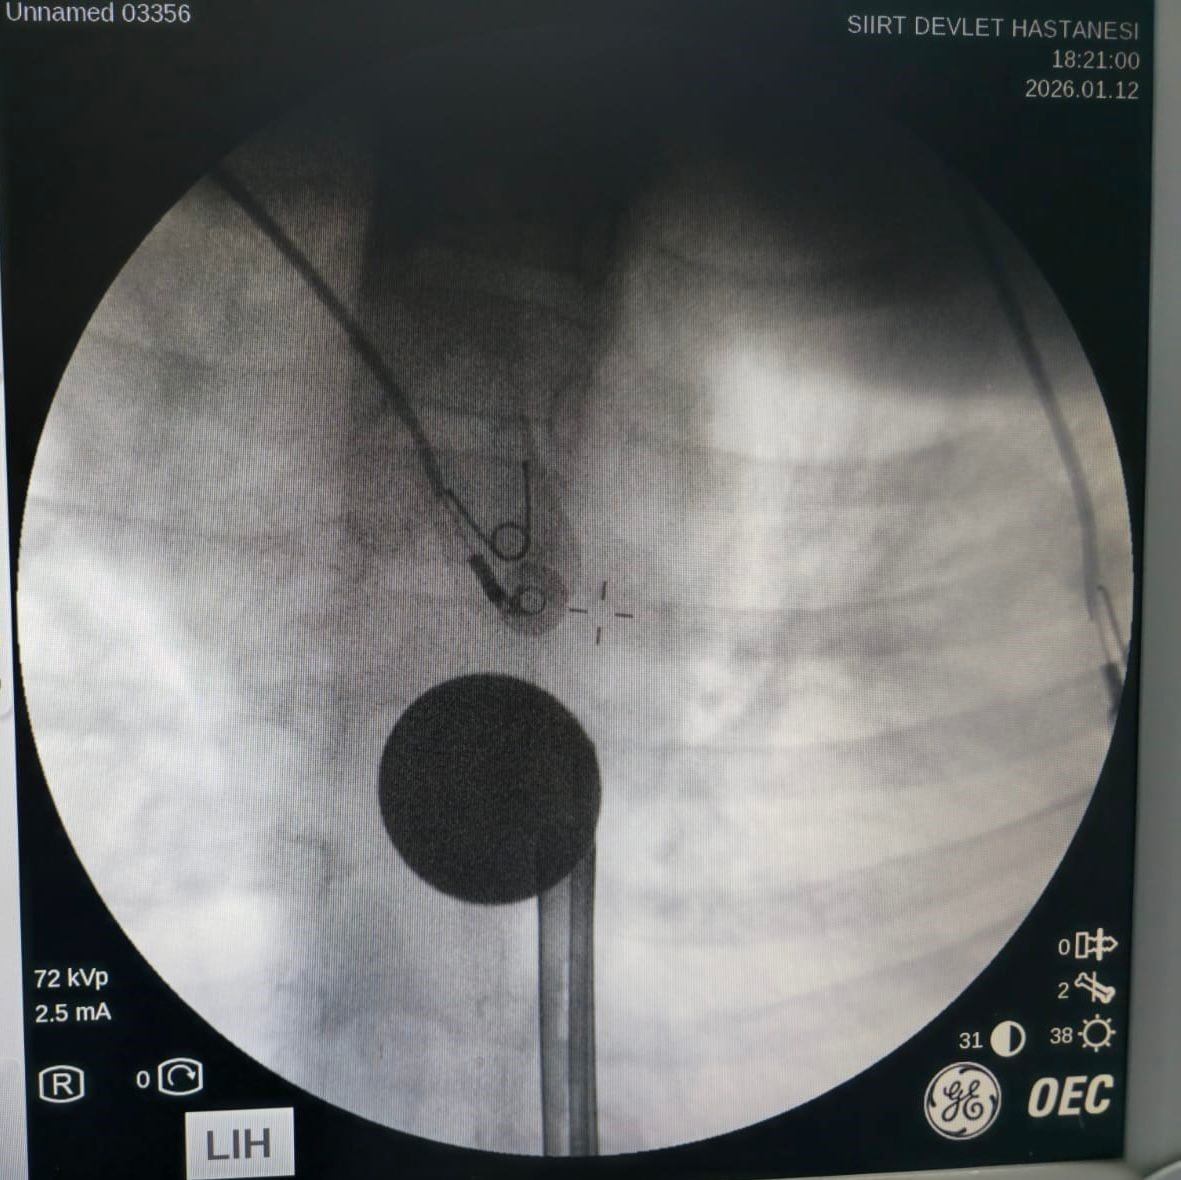

Ailesi tarafından hastaneye getirilen çocuk, yabancı cisim yutma şikayeti ile acil servise alındı. Yapılan detaylı incelemeler sonucunda, madeni paranın yemek borusuna kadar ilerlediği belirlendi. Uzman ekip, gastroenteroloji doktoru Dr. Yaren Dirik ve kulak burun boğaz hekimi Yasin Gökçınar tarafından gerçekleştirilen operasyonla para çıkarıldı.

Başhekim Yardımcısının Açıklamaları

Siirt Eğitim ve Araştırma Hastanesi Başhekim Yardımcısı Uzman Dr. Burak Özkan, çocuklarda yabancı cisim yutma vakalarının ciddi riskler taşıdığını vurgulayarak, "Hastanemize başvuran 8 yaşındaki hastamızın yemek borusuna kaçan madeni para, ekiplerimizin koordineli çalışması ile sorunsuz bir şekilde çıkarılmıştır. Tedavi süreci iyi geçti ve hastamız taburcu edilmiştir" şeklinde konuştu.